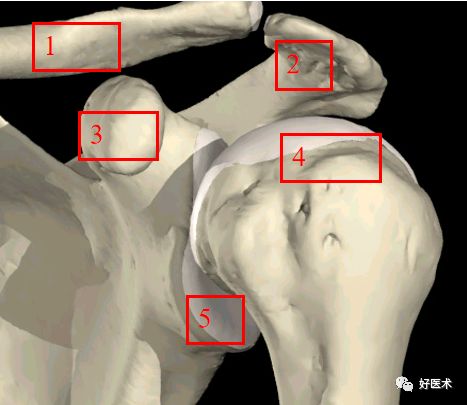

肩胛骨:

1. 锁骨

2. 肩峰

3. 喙突

4. 肱骨头

5. 关节盂